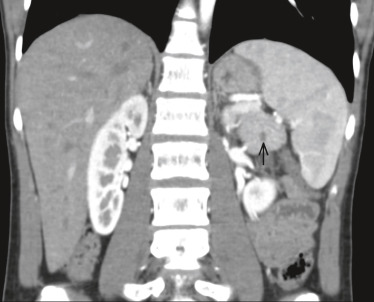

Le pancréas est fréquemment atteint dans la maladie de VHL sous la forme soit de kystes pancréatiques simples, soit de cystadénomes ( fig. 26-20), soit de tumeurs neuro-endocrines et plus rarement d'adénocarcinomes.

Parmi les autres atteintes tumorales possibles, des cystadénomes de l'épididyme ou du ligament large peuvent être responsables de troubles de la fertilité. Un phéochromocytome ( fig. 26-21), souvent bilatéral, est associé dans 11 à 20 % des cas de VHL, responsable d'hypertension artérielle paroxystique ou continue. Des tumeurs du sac endolymphatique avec une perte de l'audition dans 10 % des cas sont rapportées. Les manifestations rares peuvent être des kystes et angiomes dans le foie, la rate, les poumons ou les os, qui ne sont généralement diagnostiqués que fortuitement.

Fig. 26-20 Cystadénome pancréatique (flèche) dans le cadre d’une maladie de von Hippel-Lindau.